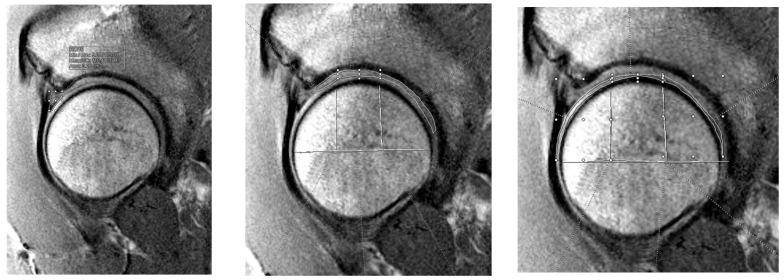

This study evaluates the relationship between preoperative cartilage quality, measured by T2 mapping, and patient-reported outcomes following labral tear treatment. We retrospectively reviewed patients aged 14-50 who underwent primary hip arthroscopy with either labral repair or reconstruction. Preoperative T2 values of femoral, acetabular, and labral tissue were assessed from MRI by blinded reviewers. International Hip Outcome Tool (iHOT-12) scores were collected preoperatively and up to two years postoperatively. Associations between T2 values and iHOT-12 scores were analyzed using univariate mixed linear models. Twenty-nine patients were included (mean age of 32.5 years, BMI 24 kg/m, 48.3% female, and 22 repairs). Across all patients, higher T2 values were associated with higher iHOT-12 scores at baseline and early postoperative timepoints (three months for cartilage and six months for labrum; < 0.05). Lower T2 values were associated with higher 12- and 24-month iHOT-12 scores across all structures ( < 0.001). Similar trends were observed within the repair and reconstruction subgroups, with delayed negative associations correlating with worse tissue quality. T2 mapping showed time-dependent correlations with iHOT-12 scores, indicating that worse cartilage or labral quality predicts poorer long-term outcomes. These findings support the utility of T2 mapping as a preoperative tool for prognosis in hip preservation surgery.

摘要

本研究评估了通过T2映射测量的术前软骨质量与盂唇撕裂治疗后患者报告的结果之间的关系。我们回顾性分析了14至50岁接受初次髋关节镜检查并进行盂唇修复或重建的患者。由不知情的评估人员从MRI评估股骨、髋臼和盂唇组织的术前T2值。收集术前及术后两年内的国际髋关节结局工具(iHOT-12)评分。使用单变量混合线性模型分析T2值与iHOT-12评分之间的关联。纳入29例患者(平均年龄32.5岁,BMI 24kg/m²,48.3%为女性,22例进行了修复)。在所有患者中,较高的T2值与基线及术后早期时间点(软骨为三个月,盂唇为六个月)较高的iHOT-12评分相关(P<0.05)。在所有结构中,较低的T2值与12个月和24个月时较高的iHOT-12评分相关(P<0.001)。在修复和重建亚组中观察到类似趋势,延迟的负相关与较差的组织质量相关。T2映射显示与iHOT-12评分存在时间依赖性相关性,表明较差的软骨或盂唇质量预示着较差的长期结局。这些发现支持T2映射作为髋关节保留手术术前预后工具的实用性。